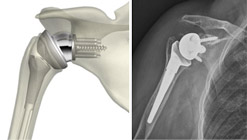

Protesi inversa: in questo tipo di protesi le componenti articolari sono invertite. L’emisfera viene impiantata nella glenoide mentre la porzione concava con cui si articola viene inserita nell’omero. Questa protesi così particolare è indicata nei pazienti con una rottura completa dei tendini della cuffia dei rotatori che quindi avrebbero un risultato funzionale dopo impianto di una protesi convenzionale non brillante. Il concetto della protesi di rivestimento è l’utilizzo del deltoide come motore della spalla in alternativa alla muscolatura della cuffia non più funzionale.

Dopo l’intervento di protesizzazione della spalla, qualunque impianto sia stato scelto, è di fondamentale importanza una precoce mobilizzazione e un programma riabilitativo intenso e specifico. Verranno subito iniziati esercizi di mobilizzazione attiva e passiva e successivamente verrà impostato un programma di rinforzo muscolare adeguato per poter ottenere da questo tipo di intervento i risultati migliori.